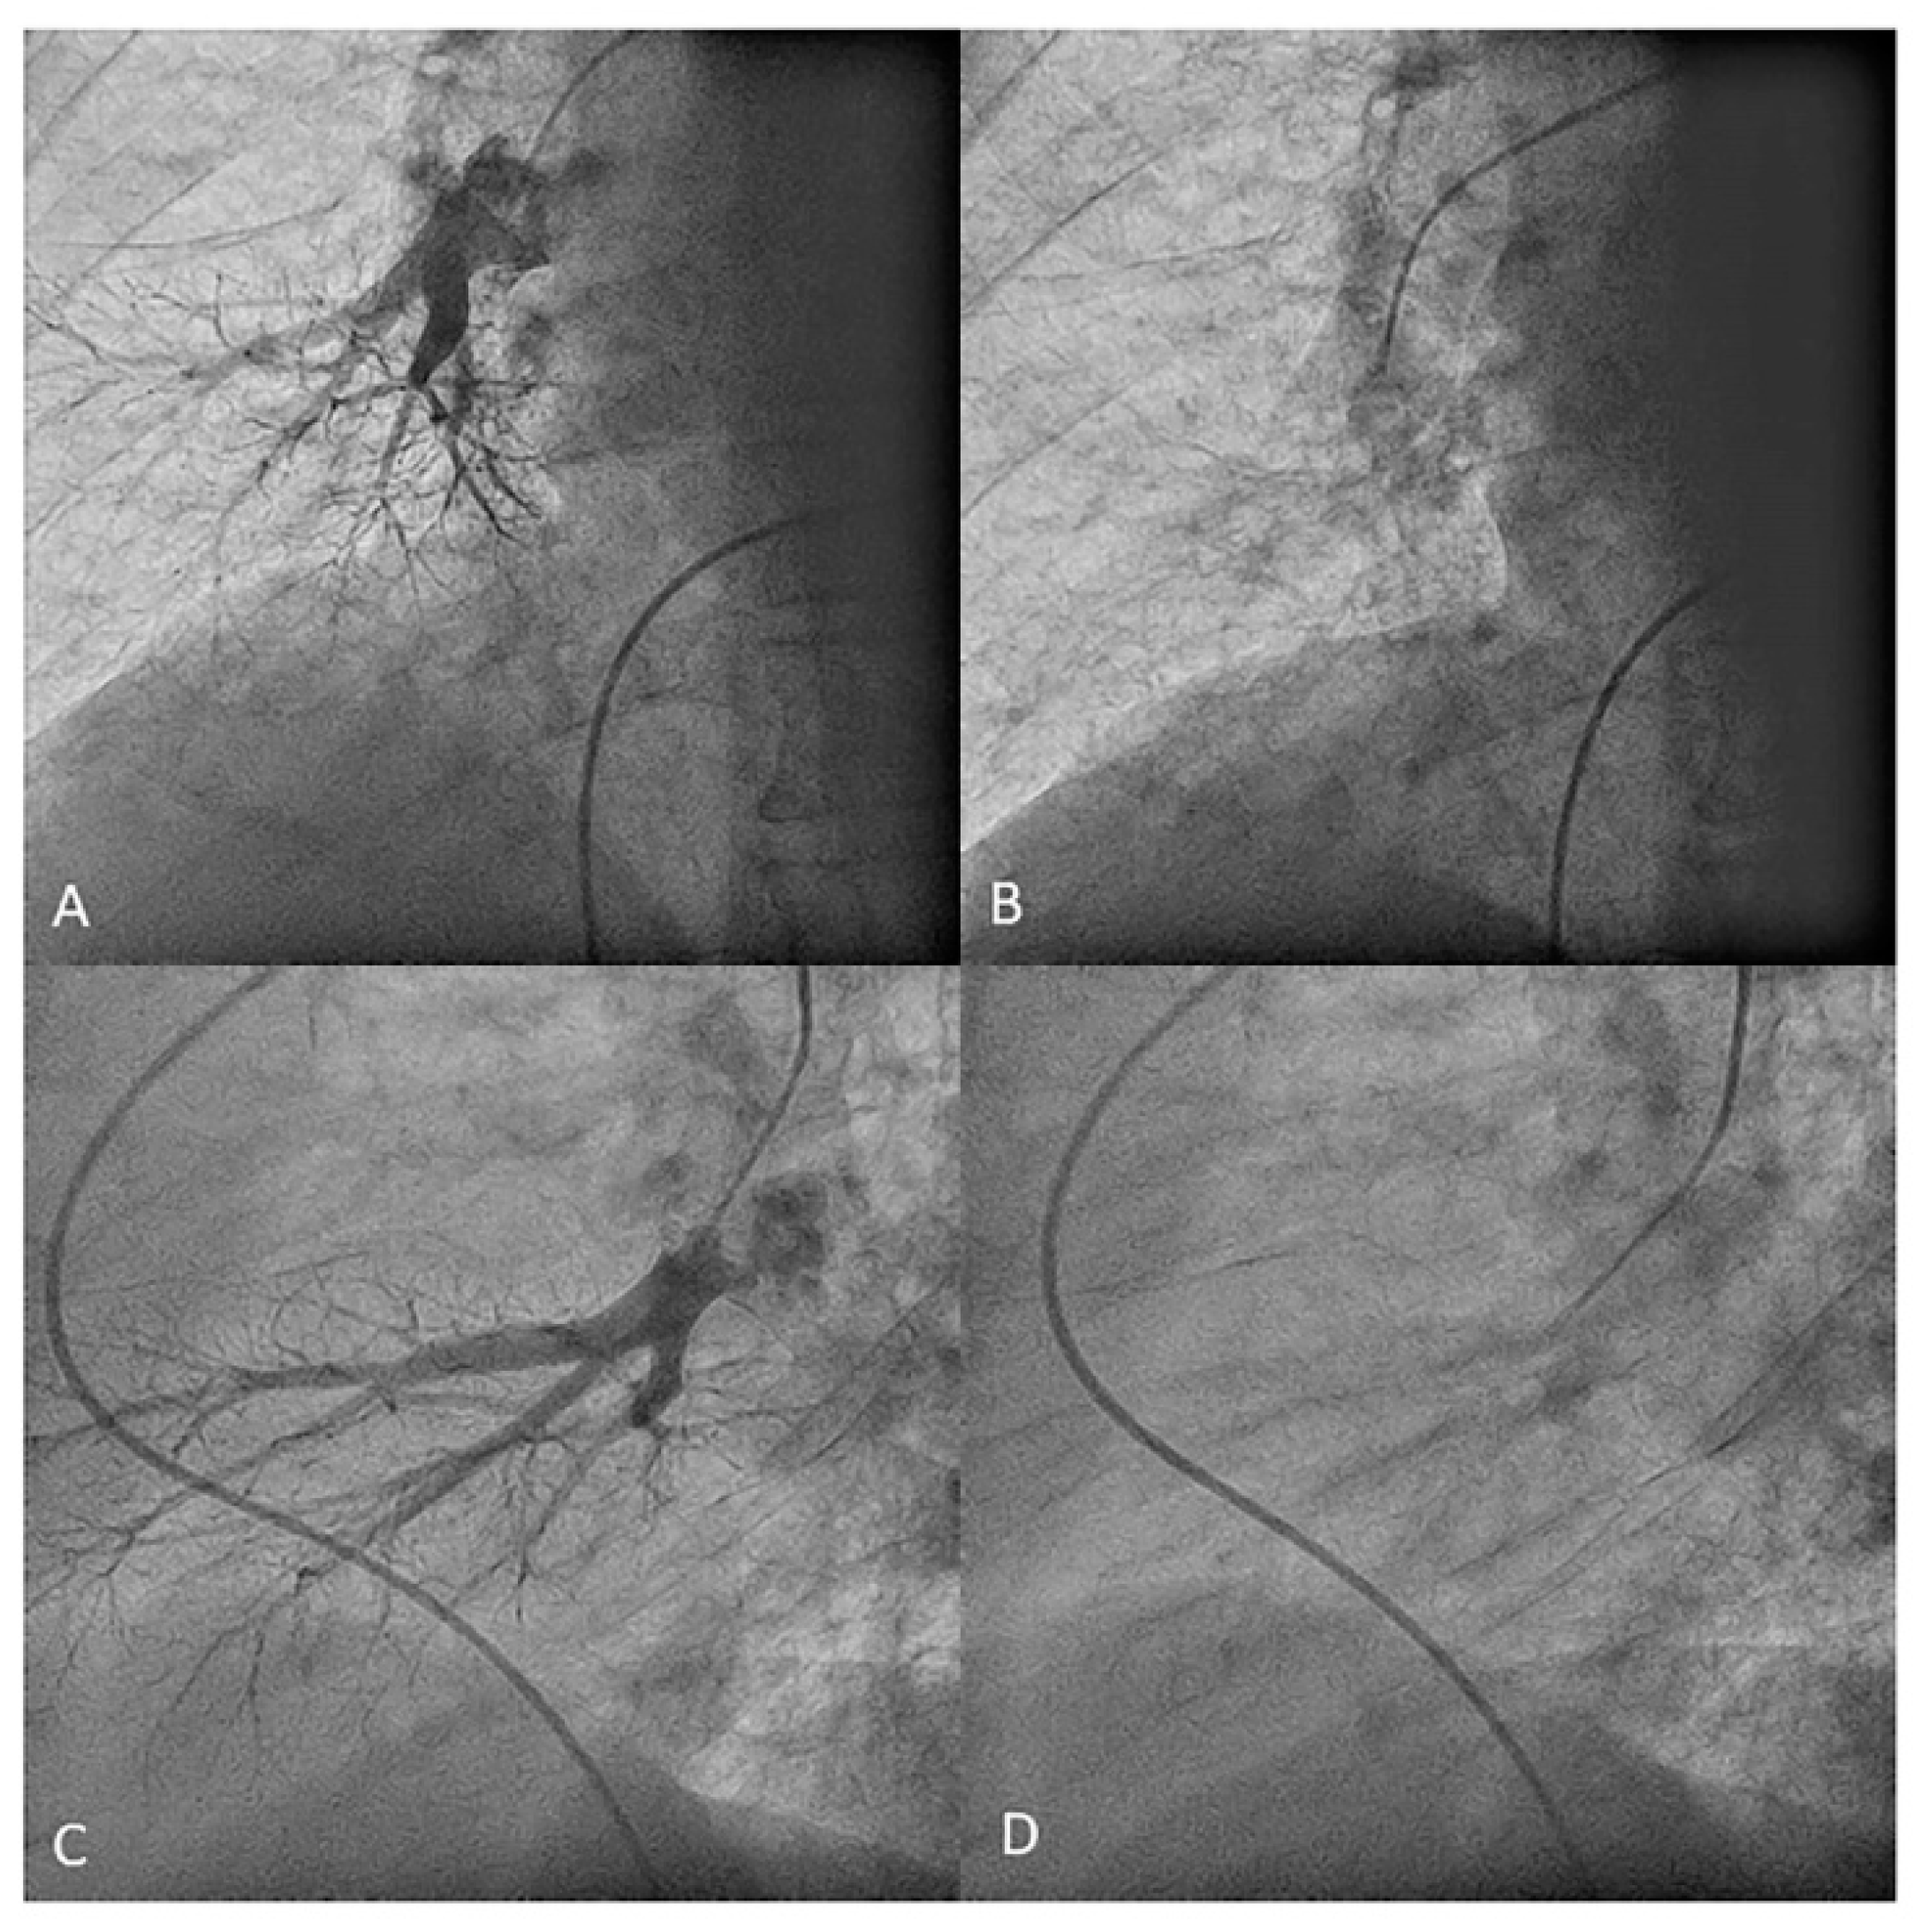

- Right upper lobe. The right upper lobar artery arises about 10 cm from the bifurcation. It is cannulated in the AP view with the tip of the MP-A2 facing upwards. The apico-posterior segmental artery (A1/2) is canalized just by advancing the MP distally once in the right upper lobe artery. The AP and lateral views display the apical (A1) and posterior branches (A2) (Figure 28). The anterior segmental artery (A3) is canalized in the lateral view, rotating the MP counterclockwise from its position in the apico-posterior artery (A1/2). With this maneuver, the tip of the catheter moves downwards, facing the sternum and engaging the anterior segmental artery (A3) (Figure 29). This branch should be filmed in lateral and cranial AP/cranial LAO view.

- Middle lobe. The middle lobe artery originates in front of the superior segmental artery of the RLL (A6), with an anterior direction, as does the lingula in the left lung (Figure 14). It is canalized with the MP, in the lateral view. The distal angulated segment of the MP should be bent, pressing against the bifurcation of the RLL, and rotated counterclockwise, with the tip of the catheter pointing towards the sternum (Figure 30). The JR 4 is also a good alternative. This artery bifurcates early in two segmental branches: lateral (A4) and medial (A5). The lateral and cranial LAO views display both branches. If these segmental branches have an independent origin in the RPA, they should be cannulated and filmed independently (Figure 31).

- Right lower lobe. The lateral projection and the MP are the best choices to canalize the two trunks of the basal pyramid and the superior segmental artery (A6). Use the AP and lateral views to assess the four segmental basal branches (Figure 32) and the lateral projection to display the superior segmental artery (A6) (Figure 16 and Figure 17).